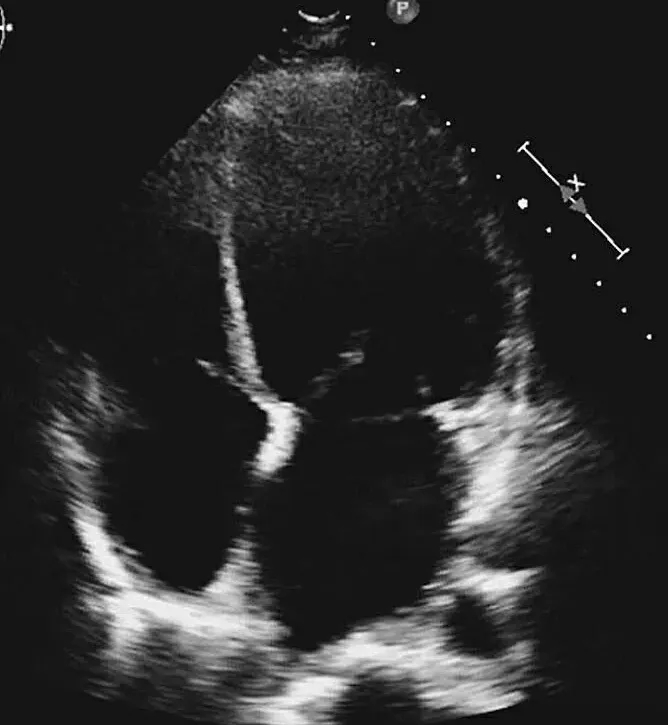

超声心动图:左心室舒张末内径64mm,LVEF 35%,右房内可见不规则条索状、团状等回声,随心脏摆动,舒张期可进入右心室,考虑右房内血栓可能,节段性室壁运动障碍(室间隔、左室心尖部、侧壁心尖段、前壁心尖段、下壁),心尖部室壁瘤形成。

给予双联抗血小板、调脂、控制心率、抗心衰及泼尼松龙60mg每日1次,并皮下注射依诺肝素强化抗凝,1周后复查心脏超声(图2),发现右房内疑似血栓影完全消失,患者也无低氧、咯血等肺栓塞临床表现。后完成CAG +光学相干成像(OCT)检查(图3),提示:左优势型,前降支近段管腔不规则发白,考虑血栓影,管腔分支稀少,血流TIMI 3级;回旋支远段节段性狭窄达90%,血流TIMI 2级;右冠细小。

图2 抗凝前后超声心动图对比

A图为入院心脏超声心尖四腔切面,可见右房内疑似血栓影,舒张期可进入右心室内;B图为抗凝治疗1周后复查,可见右房内血栓消失